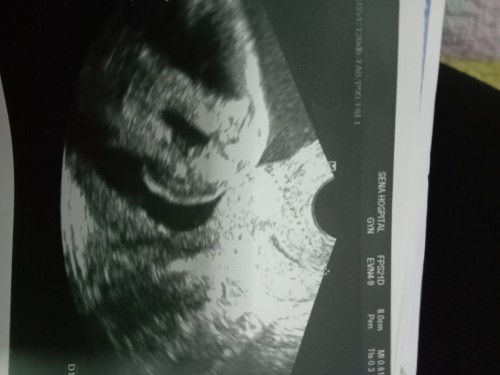

วันนี้เราไปซาวมา 20วีค พอจะช่วยเดาได้ไหมว่าเพสไหนขอบคุณล่วงหน้า🙏🙏🙏❤️❤️